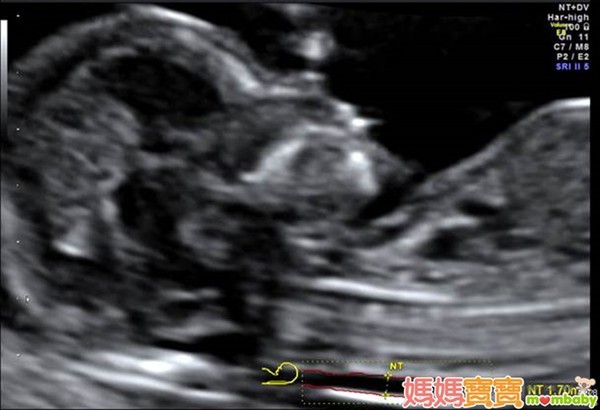

利用高解析度的超音波來檢查胎兒頸部透明帶厚度,以確認胎兒是否具備染色體或構造異常等疑慮,進而接受更進一步的評估,正是這個產檢項目的宗旨。

頸部透明帶的測量部位,為胎兒頸椎表皮與表皮底下軟組織的間隙,之所以會發展這樣的篩檢方式,是因為藉由以往的臨床經驗中逐漸得知,染色體與器官構造異常的胎兒,頸部透明帶似乎皆有變厚的傾向,例如唐氏症、透纳氏症候群、先天性心臟病等,這些疾病往往合併胎兒膠原組織組成改變,或淋巴及心血管循環出現異常,進而導致頸部透明帶變得較厚;因此,醫界便開始利用這個現象來回推檢測,觀察頸部透明帶較厚的胎兒是否有較高機率發生異狀,才會演變為現今的胎兒頸部透明帶篩檢。

頸部透明帶的檢查週數為懷孕第11週~第13週又6天之間,有些準媽媽可能會以月經週期來推算懷孕週數,但如果忘了最後一次的月經日期或平常月經不規則的孕婦,醫師會利用超音波來測量胎兒的頭臀徑(頭到臀部的長度,也就是胎兒坐姿高度),若頭臀徑介於36~84公厘之間,也達到適合檢查頸部透明帶的標準。